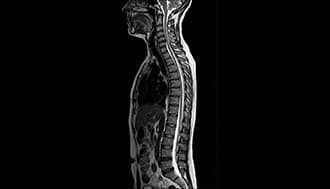

Cent combines full-body MRI, CT Calcium Scoring, DEXA, and 100+ blood biomarkers to detect diseases early - revelaing what blood tests often miss.

Full-Body MRI

Scans your entire body for cancers and structural issues.Detects problems early without any radiation.